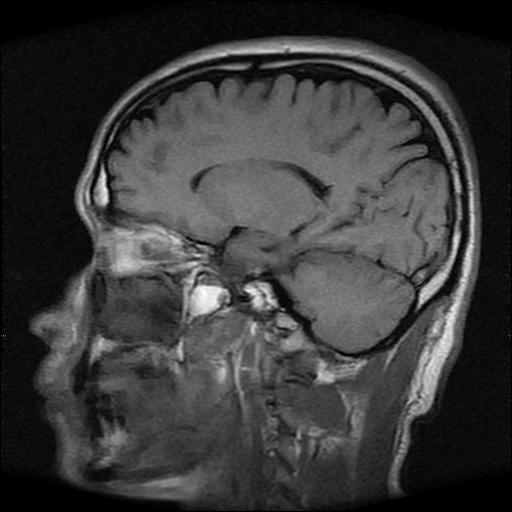

标题: MRI2584:静脉窦血栓?请会诊!

男性,39岁。头晕,视物模糊2月余。血压142/85。矢状窦内高信号有问题吗?

正常脂肪信号影。

正常,若不放心,可以mrv证实

这种病例以前也见过, 但平常的阅片过程比较少注意,而且一些资料上介绍或者图片也比较少,我觉得此病例应该考虑静脉窦血栓。

起码近来我注意的正常人静脉窦内部不是如此信号。

t1wi像可以出现缓慢流速血管呈高信号,应加t2wi及mrv